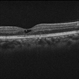

- 60 year old female with an end-stage proliferative macular telangiectasia type 2 with right-angle retinal vessels, manifested as blunted arterioles and venules that connect the superficial and deeper retinal plexus, chorioretinal anastomosis with a fibrovascular scar and a typical retinal pigment hyperplasia , fellow eye showed a focal discontinuity in the ellipsoid zone with a loss of the outer and a disorganization of the inner retinal layers, not involving the foveal center and a non exudative neovascularization